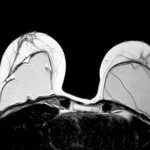

- Evaluación de implantes de seno (para determinar si los implantes de silicona se han roto).

Con la nueva RM digital podemos obtener imágenes de cada mama con saturación de grasa y además adquirir imágenes bilaterales en plano axial o sagital, lo que nos ha permitido mejorar de forma notable nuestro programa de diagnóstico por imagen del cáncer de mama.”